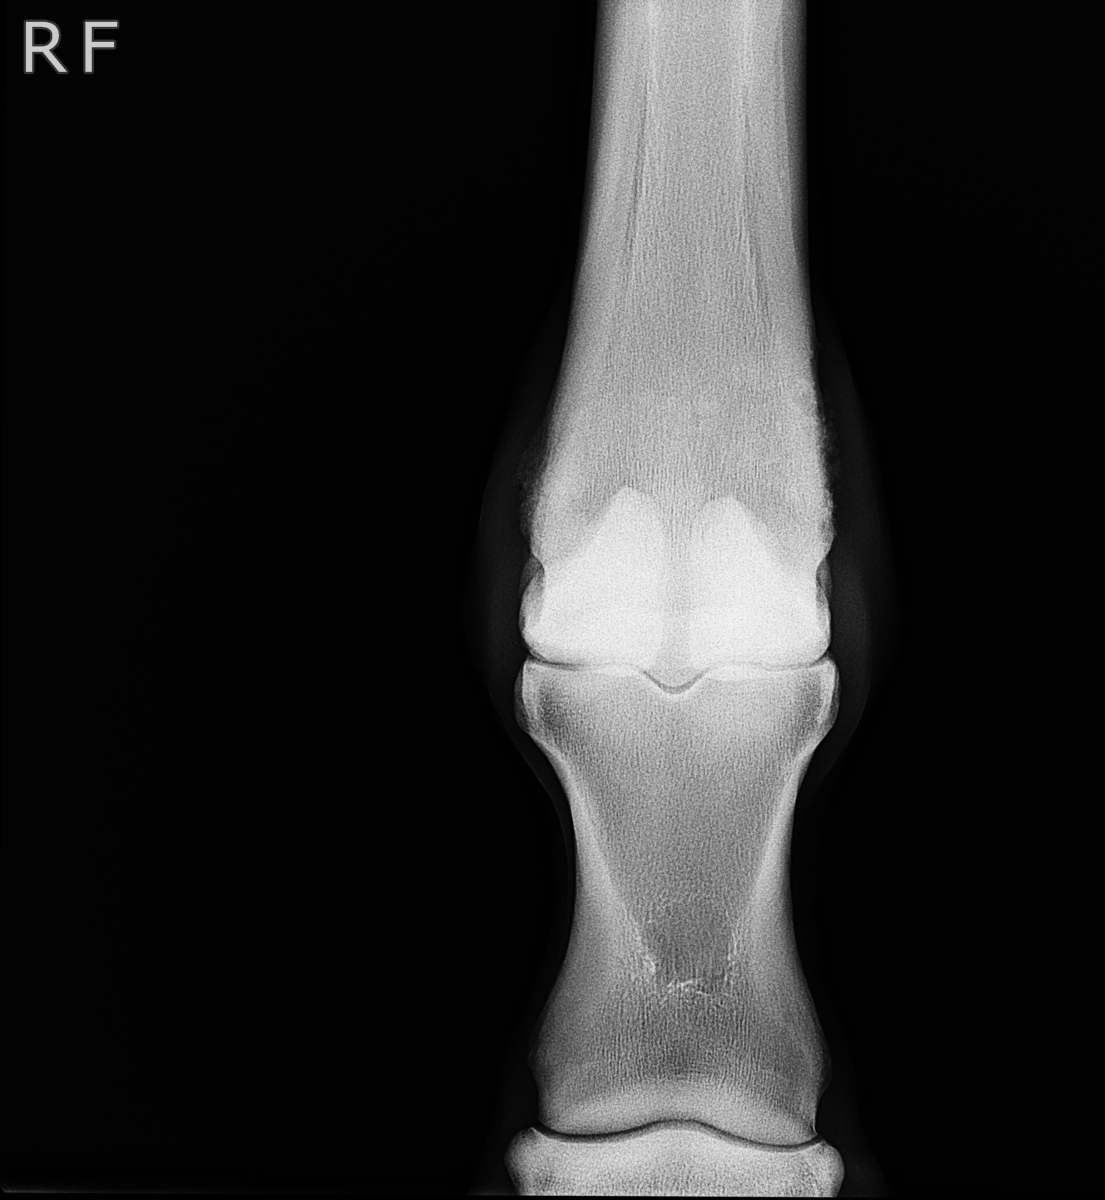

アユ号は笠松競馬、1月8日勝利後右前脚球節全面に骨膜炎が出ました。

X-Pも参考にしてください。